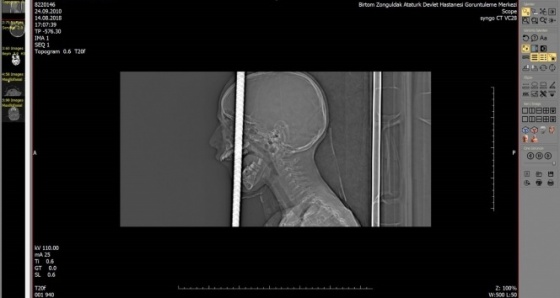

Temel prensip ilk önce zarar vermeme, üst damaktan ağız içinden giren ve yaklaşık 1 metre uzunluğundaki demir çubuk kafatasını delerek sol ön fontelden 40 santim dışarı çıkmıştı.

AFAD ekipleri tarafından 3 santim kalana kadar kesildi. Temel prensiplere bağlı kalarak parçalanan bölgeyi genişleterek demir çubuk rahatlatıldı.

Sonra ameliyata alınarak demir çubuk çıkartıldı. Ön beyin düşünce davranışlarımızı yönlendirir; hafıza, düşünme, karar verme, idare etme gibi durumları evet çocuğumuz şu an yoğun bakımda bilinci açık bir şekilde zaman içinde neyi kaybettiğini görmüş olacağız.